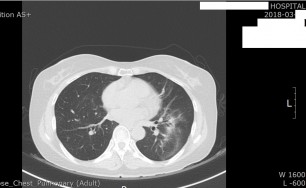

측농증

호흡기 질환만 연구, 숨케어한의원